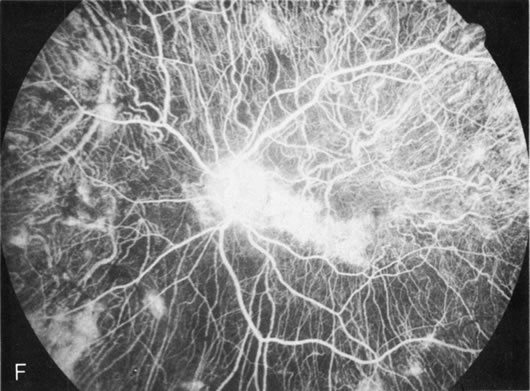

Fluorescein angiography highlights observable fundus findings. In patients with a golden reflex the FA is normal (Fig. 2E, F) or shows a mild transmission hyperfluorescence.7